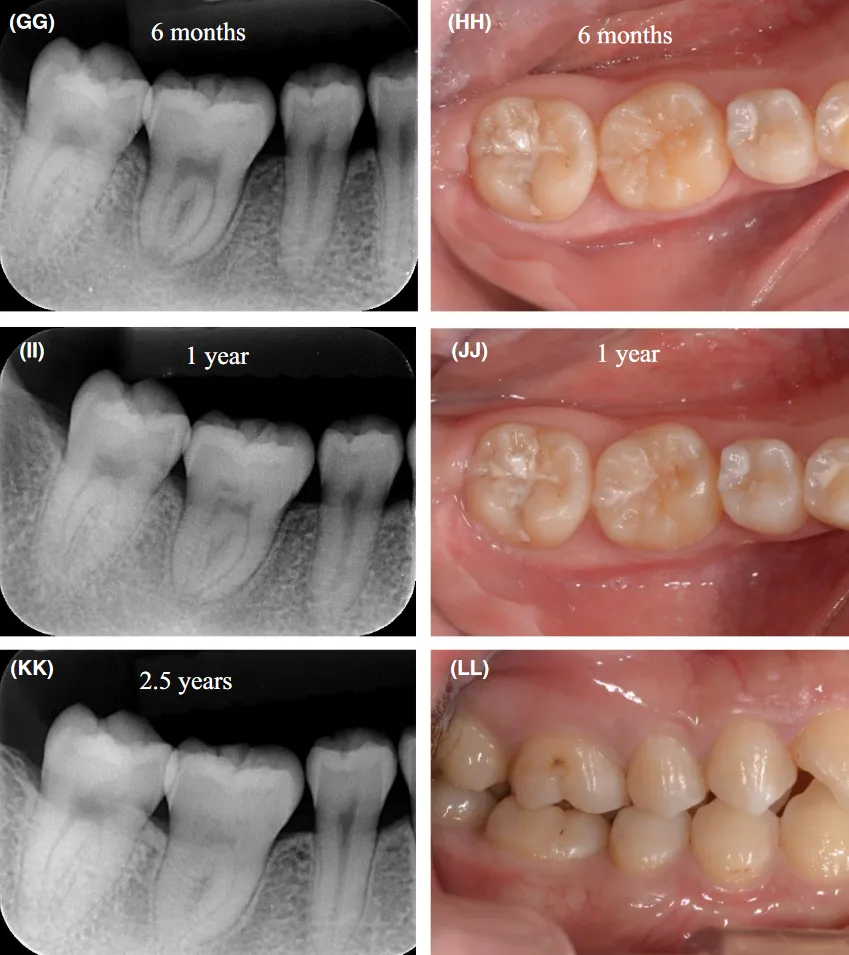

牙根发育完全的自体移植牙,根管治疗后3、6、12个月复查,此后每年复查一次;牙根未完全发育的供体牙,移植术后1、2、3、6、9、12、18、24个月复查,之后每年复查 1 次。移植牙术后 1 年进行愈合评估,评定内容包括主观症状、临床检查和影像学检查。自体牙移植成功的标准为:

(2)临床检查:移植牙无松动,叩诊无不适,牙龈无红肿,牙周探诊深度正常,年轻恒牙牙髓活力正常;移植牙术后 3~6个月松动度在II度内、术后 6~12个月松动度在I度内的,仍有进一步稳定和成功的潜力,应于术后1年再行疗效评估。

(3)影像学检查:移植牙无进行性牙根外吸收,牙根周围有正常宽度的牙周膜间隙,可见硬骨板影像;对于未完全发育的牙齿,要求牙根继续发育形成;对发育完全的牙齿,需根管充填恰填。

图8续4:(EE)术后2个月根尖片;(FF)术后3个月根尖片;(GG)术后6个月根尖片;(HH)术后6个月口内照;(II)术后1年根尖片;(JJ)术后1年口内照;(KK)术后2.5年根尖片;(LL)术后2.5年咬合照

以上成功指标中任意一项出现异常,就可判定自体牙移植失败。如出现相关临床症状或体征,影像学检查显示牙根未继续发育、根尖周透射影、牙根有进行性的外吸收等。未满足上述成功条件,但仍存留在口腔内能行使部分功能的移植牙,如有I~II度松动,周围软组织有炎症表现,牙根及其周围骨组织有不同程度吸收,与口腔内成功的移植牙合称为留存牙。

自体牙移植术的成功率虽略低于存留率,但二者均达到了临床应用标准。Meta分析显示,自体牙移植术的成功率为89.4%,存留率为96.1%。研究显示,自体牙移植术后1年的存留率高达97.4%~98.0%, 5年存留率为 81%~98.2%,随着时间的延长,其存留率有下降的趋势。